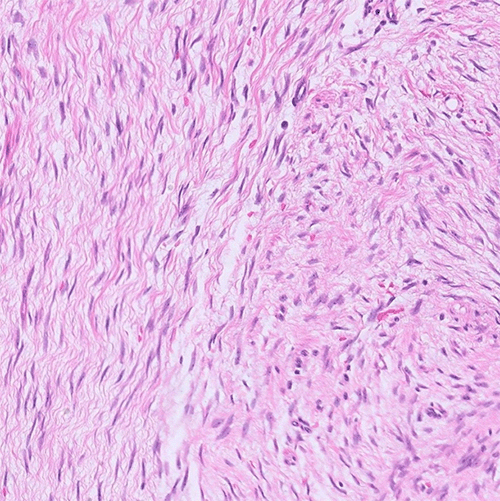

MRI further characterized the abdominal mass, revealing a 6.8 cm lesion arising from the proximal jejunal wall near the left upper quadrant gastrojejunostomy anastomosis. The mass exhibited ill-defined central enhancement with peripheral cystic degeneration, suggestive of a small bowel neoplasm (Figure 2). Based on these imaging findings, a provisional diagnosis of gastrointestinal stromal tumor (GIST) was favored. Percutaneous or endoscopic biopsy of the mass was deferred due to concern for peritoneal seeding.

Figure 2. MRI of Abdomen and Pelvis. Published with Permission

A left upper abdominal mass measuring 6.8 × 5.6 × 6.8 cm is observed to originate from a proximal jejunal loop in close proximity to the gastrojejunostomy anastomosis. The lesion displays ill-defined central enhancement near its attachment to the small bowel, surrounded by T2 hyperintense cystic contents and a peripheral T2 hypointense rim. Panels A and B depict horizontal and coronal views, respectively